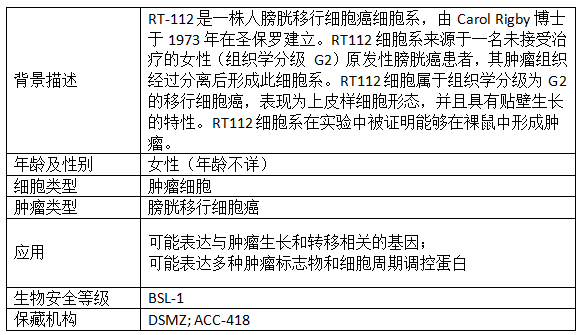

产品信息: